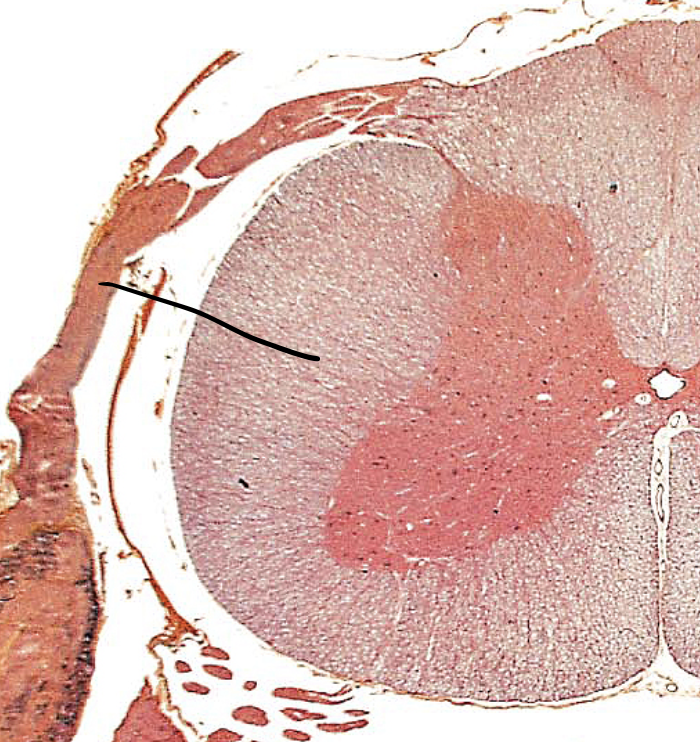

meninges

three layers of connective tissue in which the brain and spinal cord are wrapped/ The WHOLE LAYER

epidural space

The yellow stuff on TOP Cushion of fat and network of veins in space between vertebrae and spinal dura mater

dura mater

pink layer

arachnoid mater

the light blue layer

subarachnoid space

The spaces between the purple/ The blue

pia mater

The first top layer/ under the purple stuff

dorsal root

the sensory branch of each spinal nerve

dorsal root ganglion

contains cell bodies of sensory neurons

ventral root

the basal branch of each spinal nerve; carries motor neurons

spinal nerve

a peripheral nerve attached to the spinal cord. Motor and Sensor nerve.